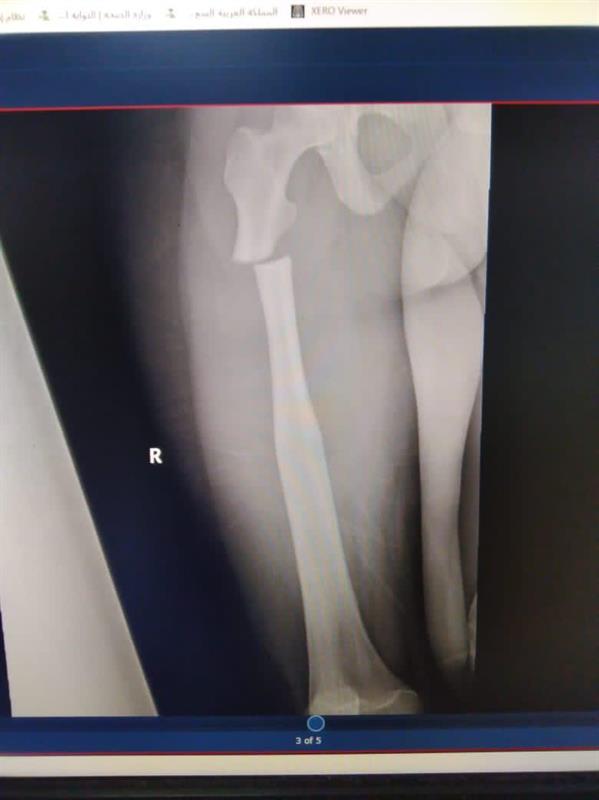

وأوضح مستشفى الدوادمي أنه استقبل شاباً وفتاة في الخامسة عشرة من العمر، يعانيّان مرضا نادرا جدا في العظم يصيب واحدا من كل 250 ألفا وهو تصخر العظم "العظم الرخامي"، حيث يكون العظم صلبا كالصخر وبنيته البيولوجية مختلة قابلة للتكسر بسهولة، إضافة لعدم وجود قناة نخاعية داخل العظم.

وأضاف المستشفى أنه لا توجد توصيات علمية عالمية ثابتة للتعامل مع هذه الكسور لصعوبة الإجراءات التقنية بل واستحالتها، لما تحمله من مخاطر جمة قد تتمخض عن أي وسيلة جراحية للتثبيت.

وأبان أن فريقا جراحيا بقيادة استشاري جراحة العظام الدكتور فؤاد البطاح، قام بتثبيت الكسور عند المصابين باستخدام سيخ تيتانيوم نخاعي متشابك في حالة، واستخدام شريحة تيتانيوم متشابكة في الحالة الأخرى، وذلك دون حدوث مضاعفات قبل أو بعد العملية، وتم خروج المريضين وهما يتمتعان بتلاشي الألم والتمكن من الحركة باستخدام وسائل مساعدة.